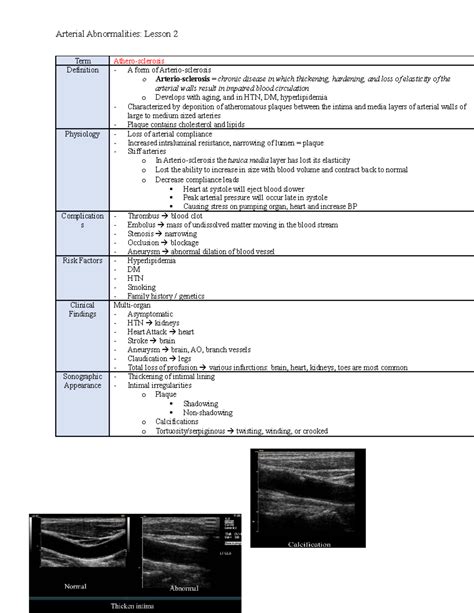

Atherosclerosis is a progressive disease characterized by the hardening and narrowing of the arteries due to the accumulation of plaques. This condition can affect any artery in the body, but it is most commonly associated with the coronary arteries, which supply blood to the heart. The process of atherosclerosis involves several stages:

• Endothelial Dysfunction: The inner lining of the arteries, known as the endothelium, becomes damaged due to factors such as high blood pressure, high cholesterol, smoking, and diabetes.

• Inflammation: The damaged endothelium triggers an inflammatory response, leading to the recruitment of immune cells to the site of injury.

• Plaque Formation: Immune cells and other substances accumulate in the artery wall, forming a plaque. Over time, this plaque can grow and harden, narrowing the artery and reducing blood flow.

• Complications: The plaque can rupture, leading to the formation of a blood clot that can block the artery completely, causing a heart attack or stroke.